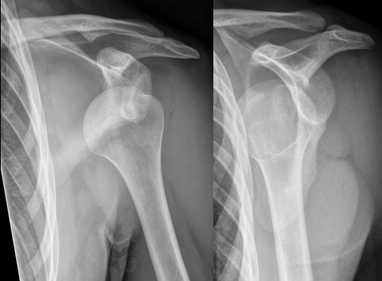

Shoulder Dislocation – Causes, Symptoms, and Recovery By Dr. Kashyap Solanki, Orthopaedic Surgeon, Andheri East, Mumbai

Introduction The shoulder joint is the most mobile joint in the human body — and because of this, it’s also the most likely to dislocate....